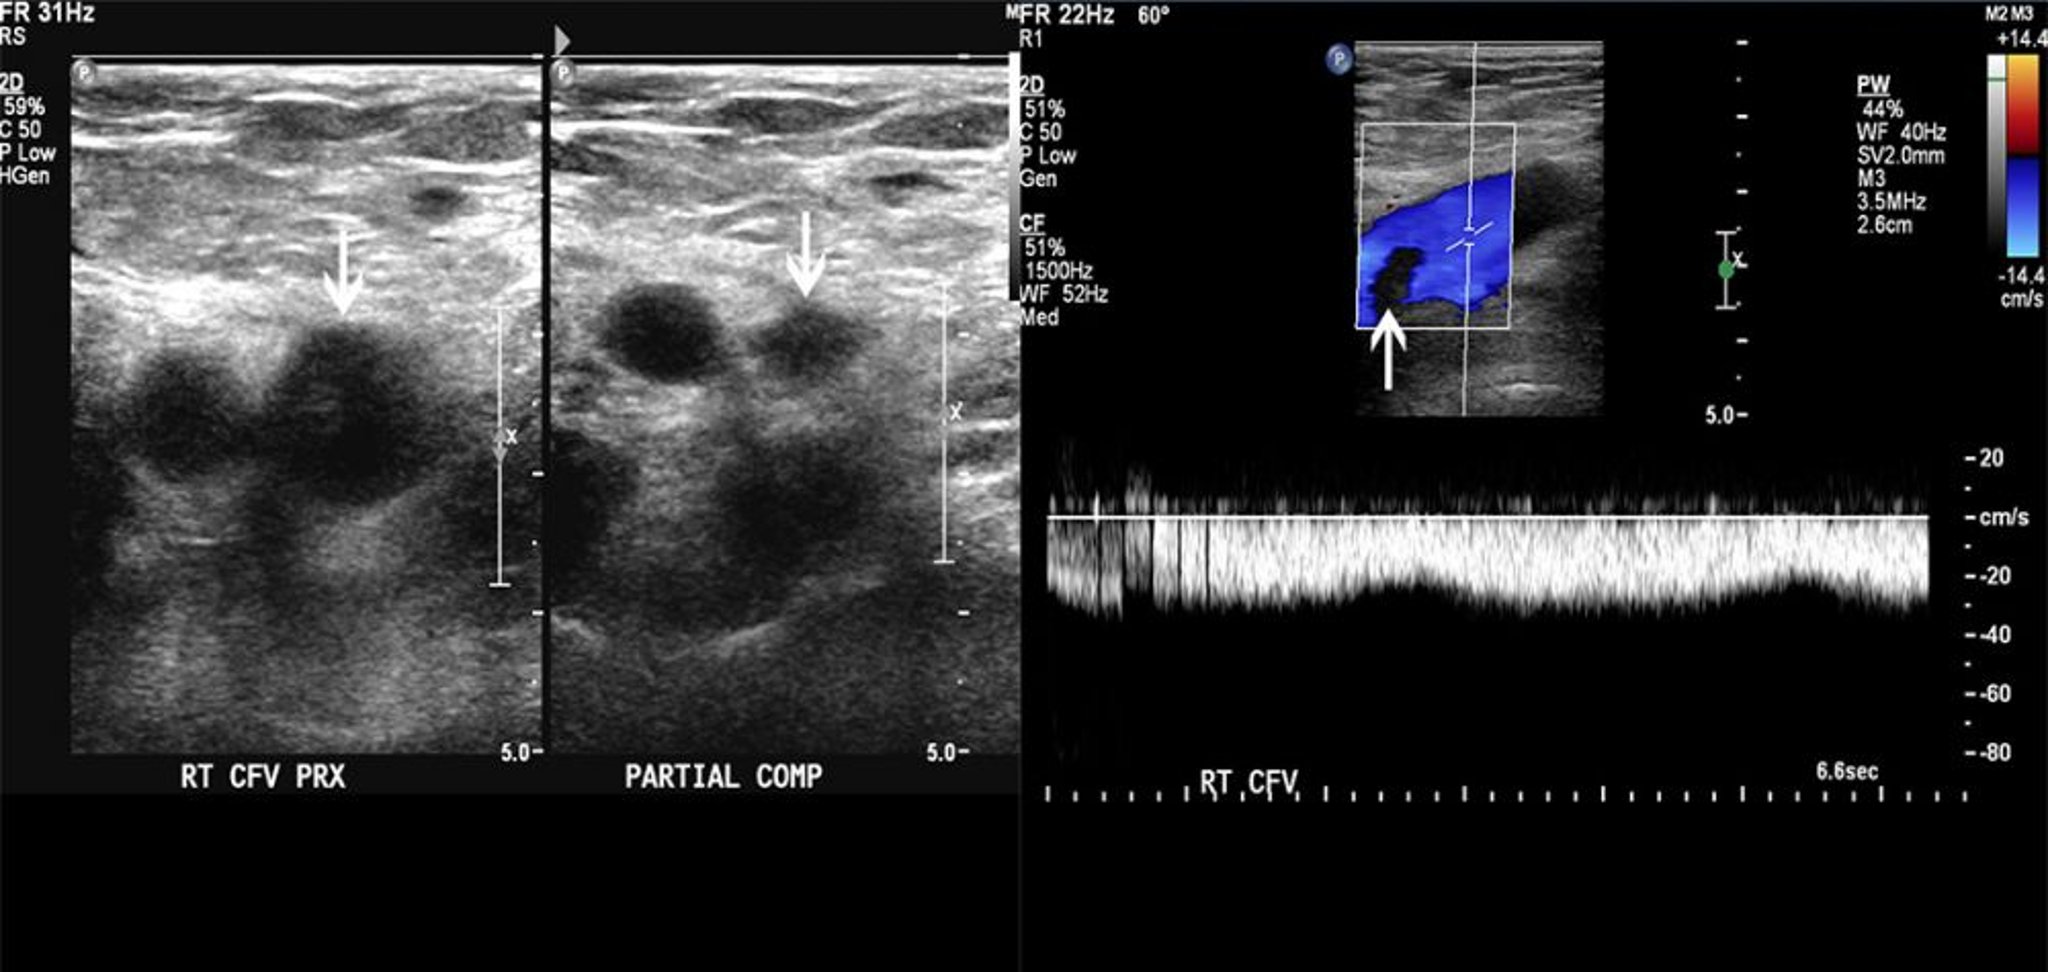

Ecografía Doppler de un paciente con un trombo en la vena femoral

La imagen de la izquierda muestra la compresibilidad parcial de la vena femoral común (flechas). La imagen de la derecha muestra un defecto de llenado en el flujo Doppler color. Estos hallazgos son compatibles con un trombo.